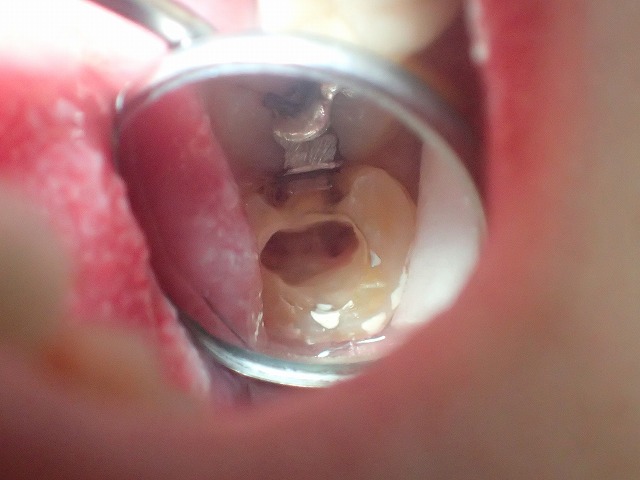

引き続きレジン充填を除去します。

かなり除去しましたが

黒さの判定・・・おそらく過去に充填された金属が

参加されて金属イオン溶出して歯を

黒く着色していると判断。

さらに除去すると二次象牙質で

髄腔はカチカチ

限界まで虫歯を除去したのち

抗菌剤と特殊なジェルを練和して

虫歯菌に対応。